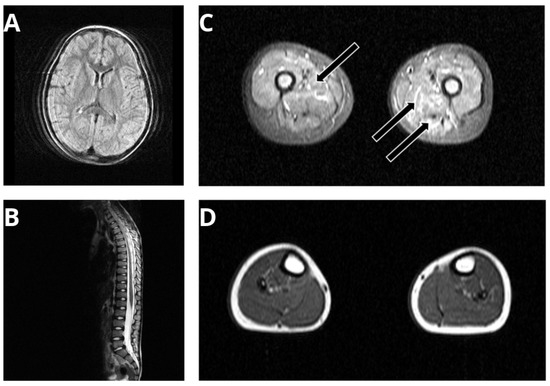

3.1. Phenotyping of a SPTLC1-Related ALS Case with Juvenile Onset

4.1. Clinical and Microscopic Findings of the p.(A20S)-SPTLC1-Patient